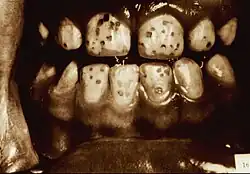

Dental fluorosis appears as a range of visual changes in enamel[4] causing degrees of intrinsic tooth discoloration, and, in some cases, physical damage to the teeth. The severity of the condition is dependent on the dose, duration, and age of the individual during the exposure.[1] The "very mild" (and most common) form of fluorosis, is characterized by small, opaque, "paper white" areas scattered irregularly over the tooth, covering less than 25% of the tooth surface. In the "mild" form of the disease, these mottled patches can involve up to half of the surface area of the teeth. When fluorosis is moderate, all of the surfaces of the teeth are mottled and teeth may be ground down and brown stains frequently "disfigure" the teeth. Severe fluorosis is characterized by brown discoloration and discrete or confluent pitting; brown stains are widespread and teeth often present a corroded-looking appearance.[1]

| Severe | 5 | All enamel surfaces are affected and hypoplasia is so marked that the general form of the tooth may be affected. The major diagnostic sign of this classification is discrete or confluent pitting. Brown stains are widespread and teeth often present a corroded-like appearance. |